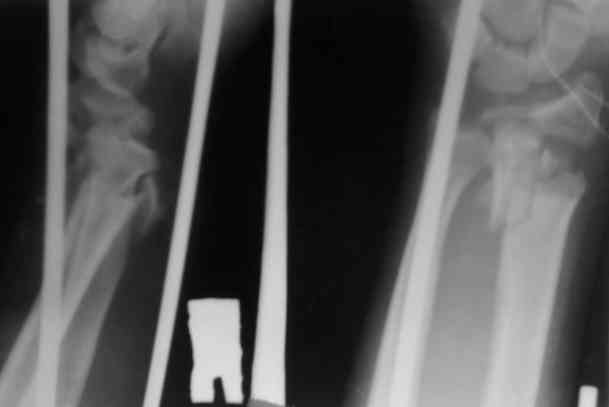

Уважаемые участники форума,поделитесь опытом...Поступил больной 23.03.07 в отделение нейрохирургии с диагнозом:кататравма, ушиб головного мозга ср.тяжести,линейный перелом лобной кости слева, открытые переломы костей обоих предплечий.

По дежурству перооперирован.На оба предплечья наложены ЧД аппараты (см. приложение)Через 3 дня переведен в травм.отделение. Мнения коллег о дальнейшей тактике разделились: накостно с трансплантацией или ЧДО аппаратом Илизарова, с целью добиться, хотя бы относительно удовлетворительного стояния.На сегоднешний день выраженный болевой синдром, больше слева.Раны на предплечье заживают первично.

Слева стояние вроде приемлемо,хотя снимки не очень информативны.

Очевилно, здесь аппаратный вариант далеко не исчерапал своих возможностей. Пока аппараты скомпонованы неоптимально - среднюю опору желательно было расположить не совсем рядом с проксимальной, а на 2-3 см выше перелома, закрепив на ней единственную спицу с упором, которая позволила бы управлять положением центрального

отломка лучевой кости.

По левому предплечью - суставной конец лучевой кости выглядит неплохо, больших ступенек не видно, так что можно попытаться 2-3 спицами с упорами встречно фиксировать эпиматефиз лучвой кости, установить на этом уровне кольцо, ссбросить перерастяжение и вскоре освободить кисть. В локтевую провести 2 спиц с упорами (сразу дистальнее перелома с упором от межкостного промежутка, в головку - встречно, закрепить на консольных приставкх на ту опору, которая сейчас средняя.

С правым дело хуже, хотя и в этом случае суставная площадка сохраняет форму, что оставляет шанс на закрытое ведение. Здесь как раз бы переввести спицу в луч проксимальнее перелома (скользнув ею по тылу локтевой кости). Установить на этом уровне кольцо. Закрепить и натянуть эту спицу в полукольце большего диаметра. За это полукольцо руками (или временно соединив его стержнями перпенидкулярно оси предплечья) центральный отломок сместить к тылу до восстановления оси.

Потом аккуратно сбросить перерастяжение за кисть, и посмотреть, что получится. Если суставная площадка сохранит форму, луче-локтевые взаимоотношения будут приемлемые, можно также фиксировать 2 спицами эпифиз, и потом освободить кисть.